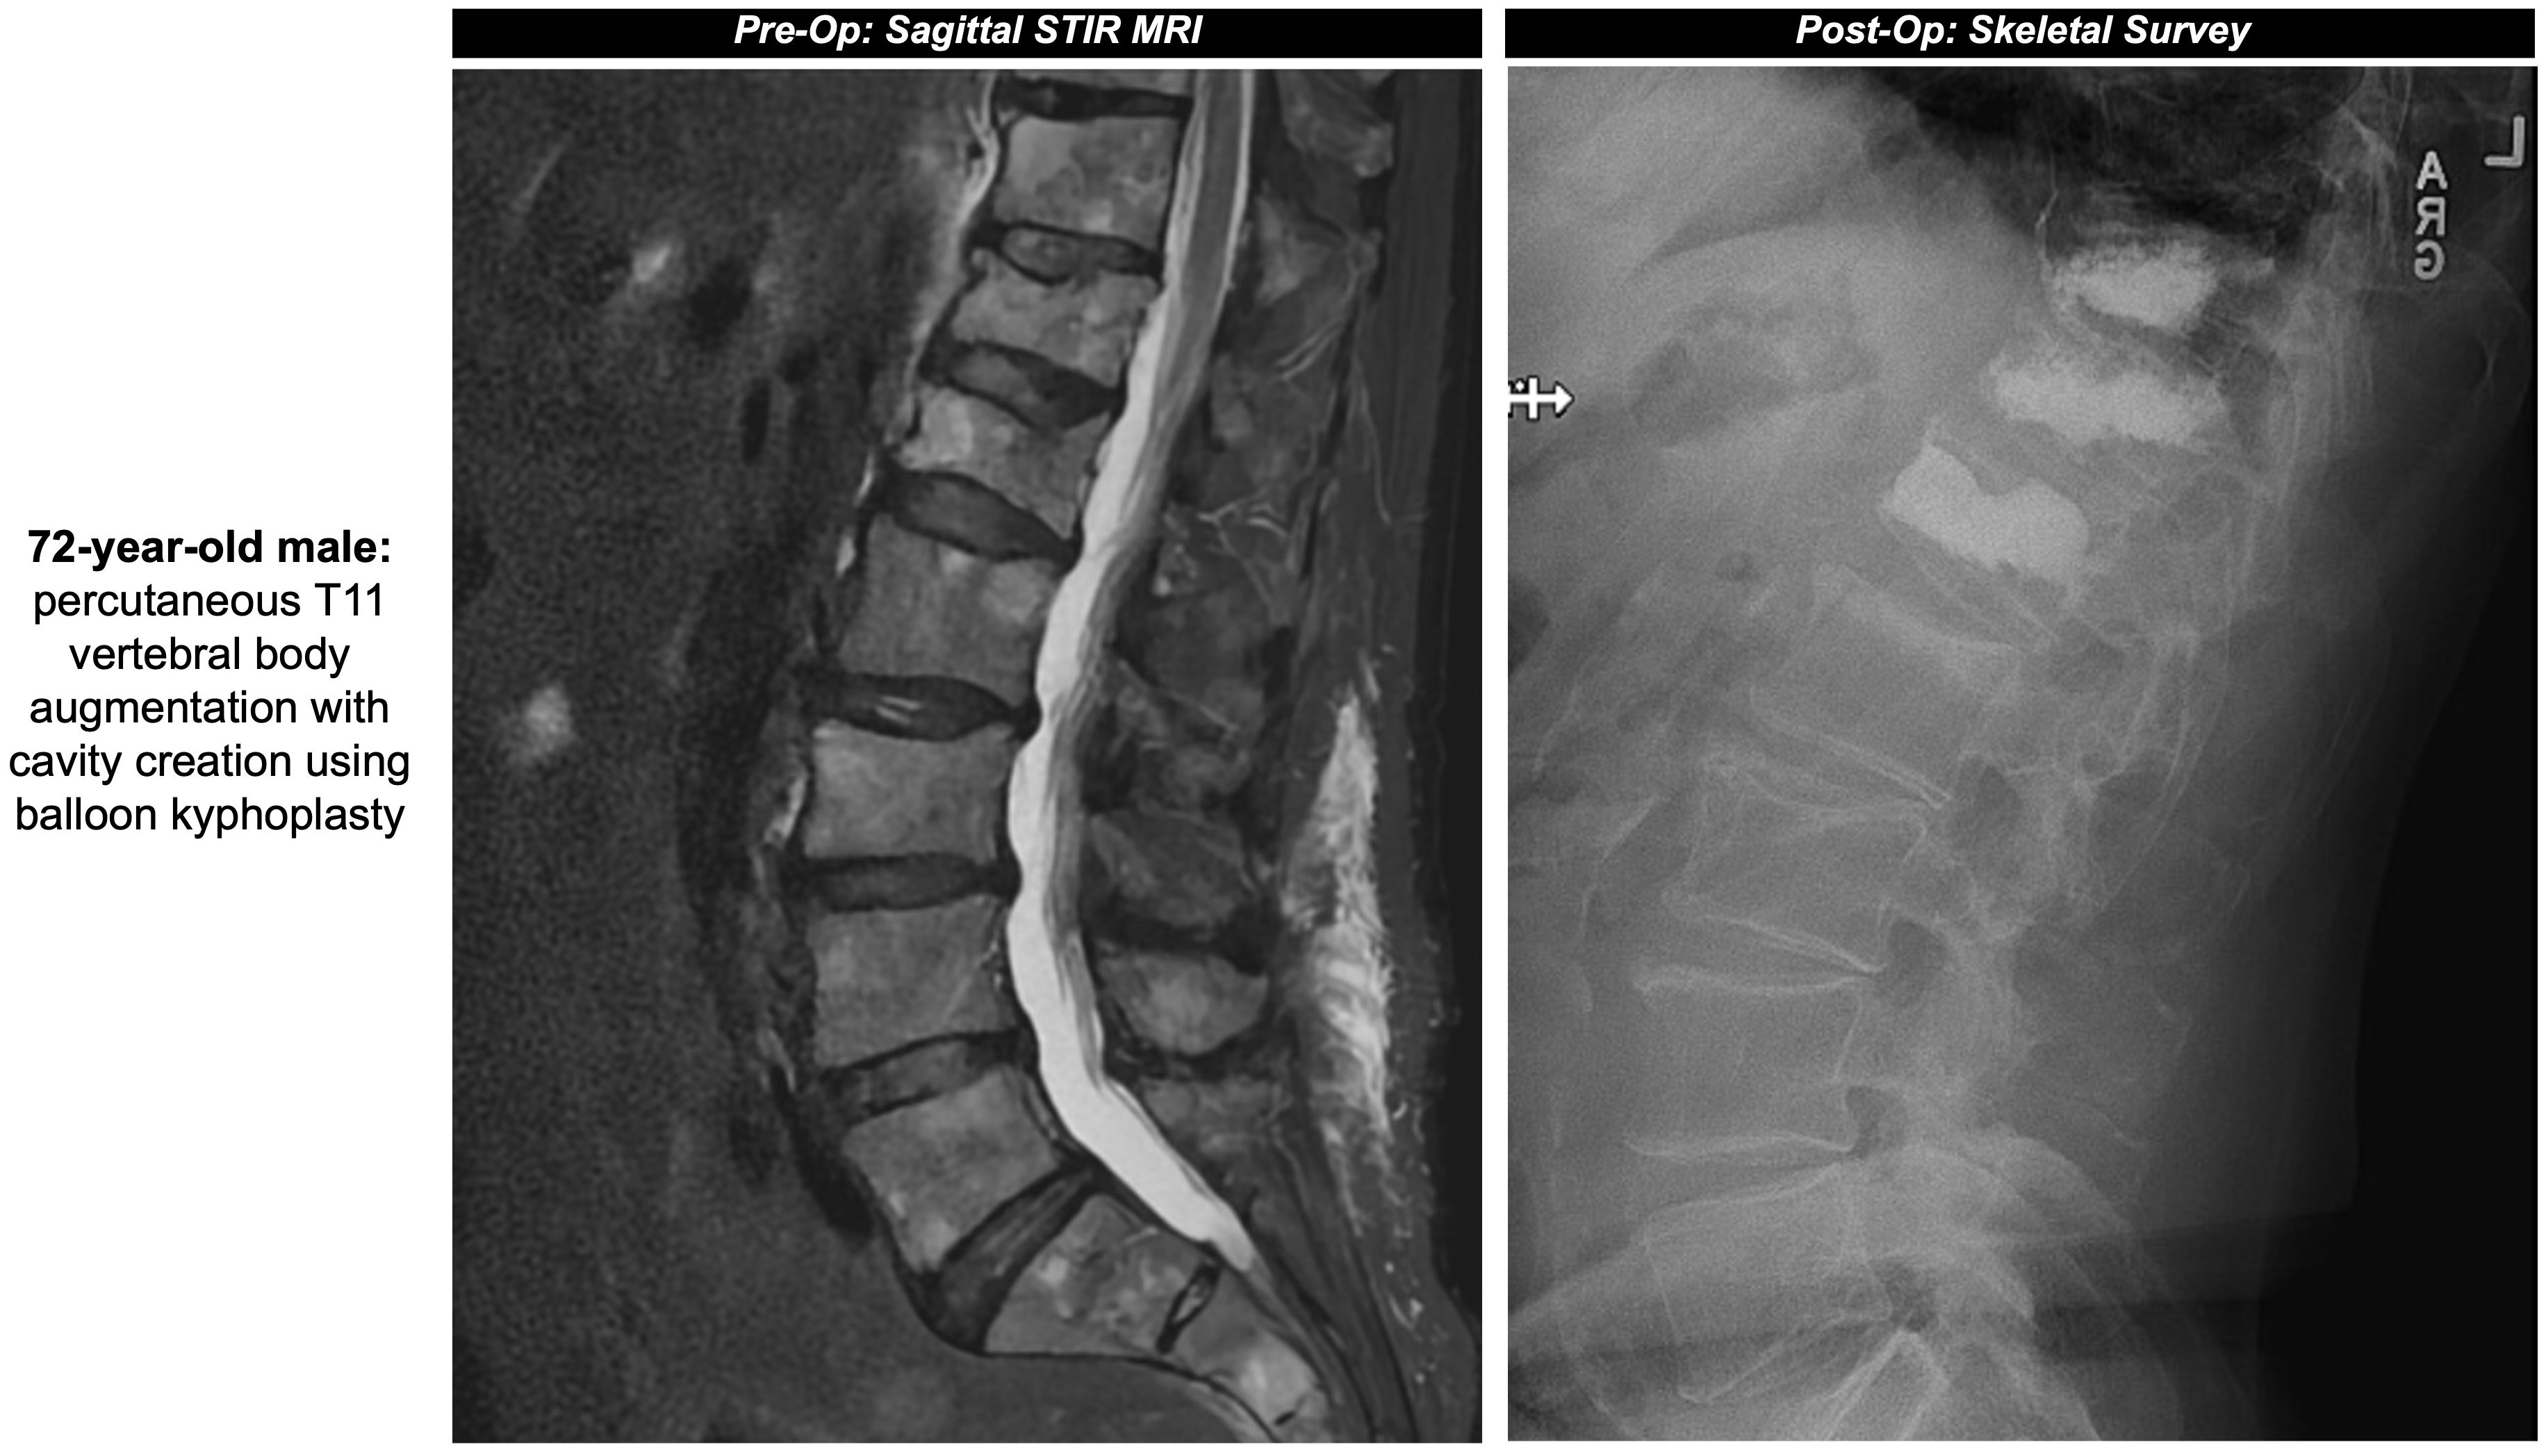

Treatment of painful, pathologic vertebral fractures in patients with MM can include vertebroplasty and kyphoplasty, particularly when lytic lesions occur in regions susceptible to compressive forces. In vertebroplasty, bone cement made up of polymethylmethacrylate (PMMA) is injected directly into the fractured vertebral body. In comparison, kyphoplasty first comprises placement of an inflatable balloon into the vertebral body with creation of a potential space or cavity, prior to injecting PMMA or absorbable calcium phosphate (13) (Figures 1A, B, 2). The primary objective of both procedures is to consolidate and stabilize pathologic bone fractures to achieve measurable pain relief. Notably, kyphoplasty also aims to restore vertebral body height via balloon inflation (3, 13). The most common complication of kyphoplasty is cement leakage, noted in 18% of treated vertebral levels in a 2009 study involving 76 MM patients. Rare but serious sequelae of leakage include motor deficits from spinal cord compression or pulmonary embolism, reported in 2% to 13% of cases (13, 14).

Figure 2. Pre- and post-operative sagittal surveys of the patient from Figure 1A.